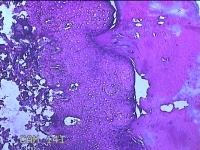

左足部包块

性别

女

年龄

34岁

临床诊断

皮下囊肿

一般病史

发现左足部包块4年余,无明显疼痛及不适。

标本名称

大体所见

灰白暗红色组织1.8x1.1x0.8cm一块,表面带梭形皮肤1.8x0.8cm,皮下见包块1。8x0.8x0.7cm一个,切开包块呈实性,切面灰白粉红色,质软。

图3